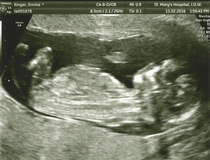

Date brought forward to August 19th so 12 + 6 today.

Little bugger was being awkward and took nearly an hour to get the NT measurements. Not complaining mind you, got to watch my baby for an hour 😍